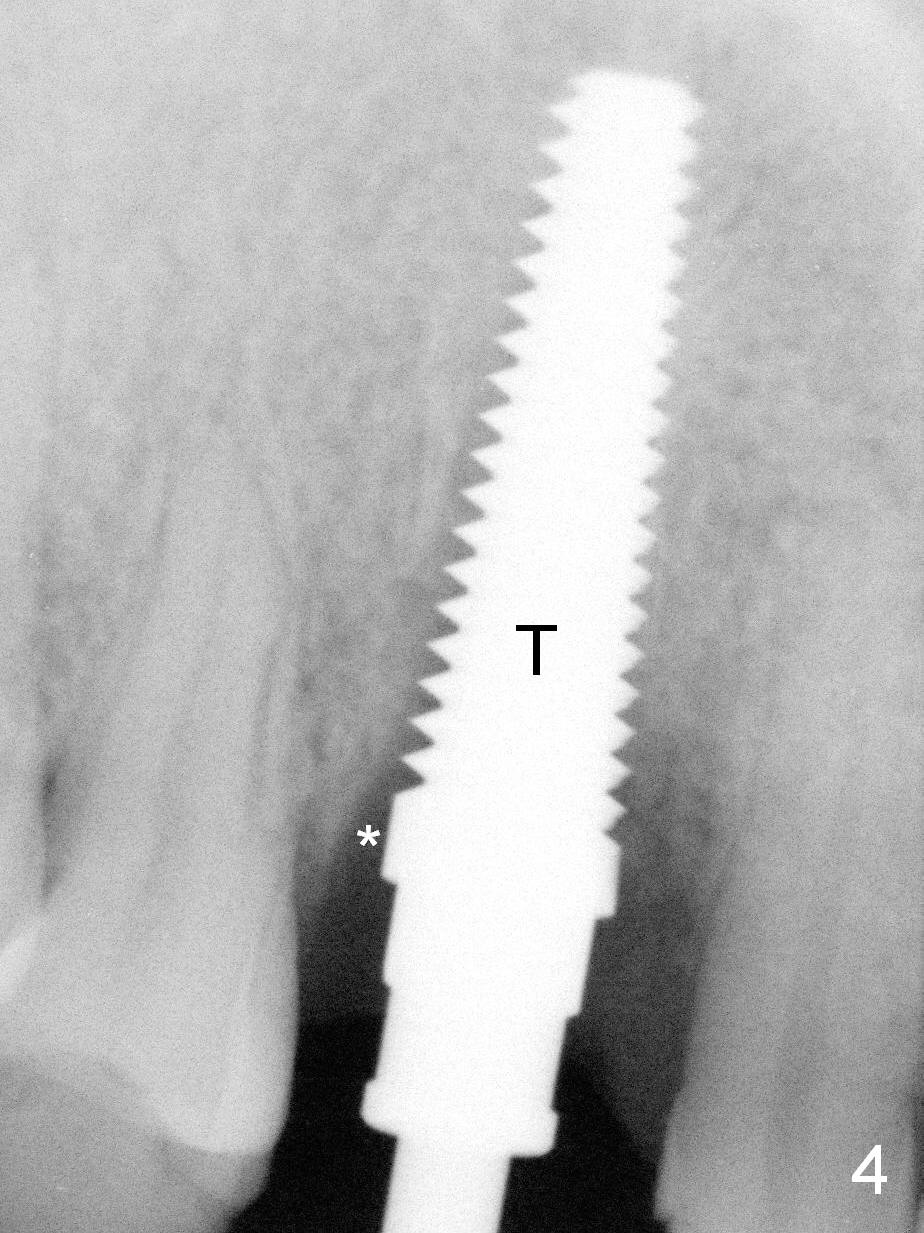

Lengthwise, a longer osteotomy is needed (Fig.4): 20 mm at the gingival level, 17 mm at the bone level. Distal to the 5 mm tap (T) is a gap (*).